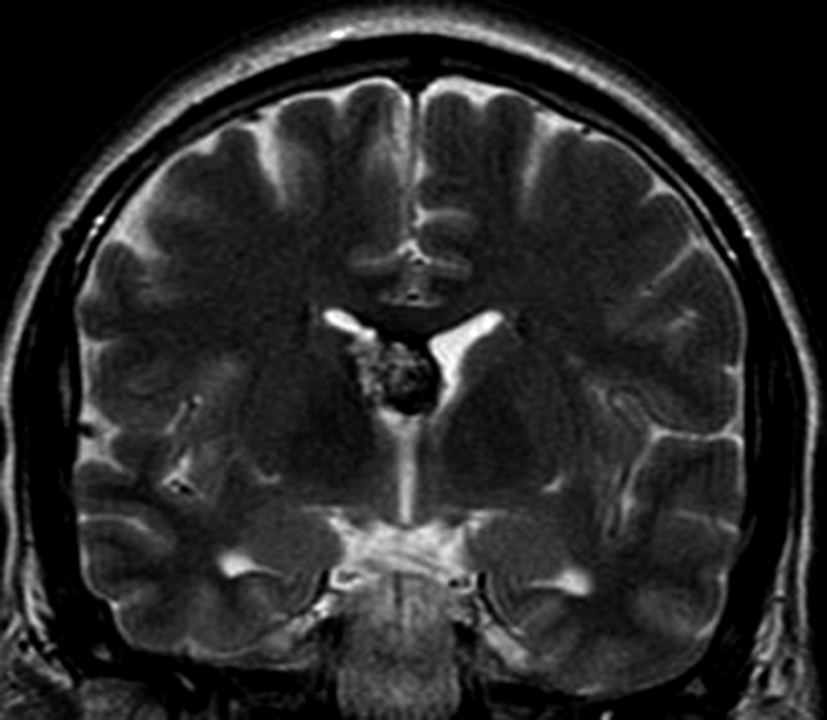

Con los hallazgos tomográficos, no se efectúan planteos diagnósticos y se realiza una resonancia magnética con la finalidad de obtener más datos semiológicos en busca de una aproximación diagnóstica. Se realizó el estudio por medio de secuencias T 1, FSE T 2, FLAIR, SWI y Difusión, en cortes axiales, FSE coronal y sagital T 1. Se realiza la administración de gadolinio DTPA en los tres planos. Se evidencia la lesión bien definida a nivel del ventrículo lateral derecho, que involucra al tronco del cuerpo calloso (Figura 2- C y 3- B). Presenta intensidad de señal heterogénea en secuencias T1 y T2 (Figura 3 y Figura 4). En secuencia ecogradiente se observa una señal marcadamente hipointensa y heterogénea, con un halo hipointenso bien definido (Figura 2- C). No presenta realce significativo tras la administración de Gadolinio (Figura 2- B) y en la secuencia de difusión no presenta restricción.

Figura 4

a y b) Imágenes coronales T2, Ay B. se evidencia la lesión con epicentro en el asta frontal del ventrículo lateral derecho y la extensión al cuero calloso.